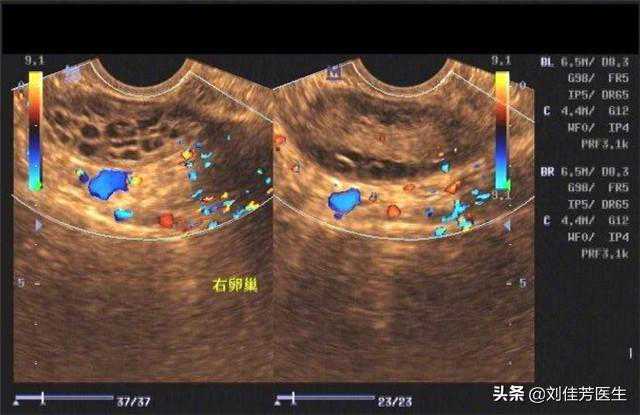

多囊女性做试管婴儿,不了解这些注意事项,就别轻易下决定

当母亲可能是每一个女性,都会有一点向往憧憬的人生之路。但是,面对众多的妇科疾病威胁,想要成为一个母亲...